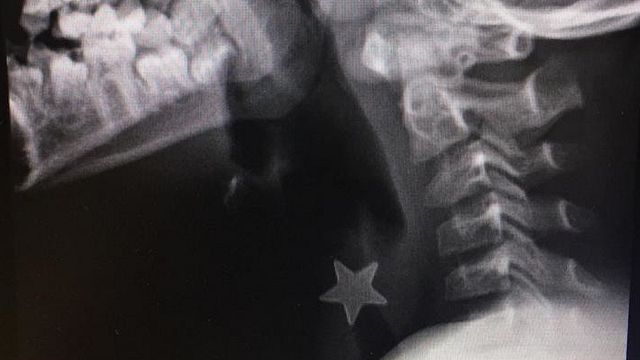

Un bambino di otto anni è stato salvato dai medici dell'ospedale di Niguarda di Milano dopo essersi presentato con una stellina di metallo del diametro di 1,5 centimetri ferma nella trachea e inalata da più di 24 ore. Il piccolo era stato inviato nella notte con un trasporto d'urgenza da un altro ospedale milanese. L'intervento è durato un'ora ed è stato eseguito utilizzando un broncoscopio di sei millimetri di diametro introdotto dalle vie aeree.

"Abbiamo deciso di intervenire nell'immediato, il piccolo infatti era gravemente asfittico nonostante la stellina fosse stata inalata da tempo, da circa un giorno - ha commentato Massimo Torre, direttore del reparto di Chirurgia Toracica -. Non si poteva aspettare oltre, alle due della notte la sala operatoria e l'equipe erano pronti per la procedura di rimozione".

Attraverso il broncoscopio, ha precosatp Serena Conforti, responsabile della Chirurgia Endoscopica del torace, "si inserisce una particolare pinza miniaturizzata con cui si va ad estrarre l'oggetto inalato. Si tratta di un'operazione molto delicata che richiede un alto grado di specializzazione per evitare danni alle strutture. In questo caso il corpo era posizionato nella parte alta della trachea appena sotto le corde vocali".